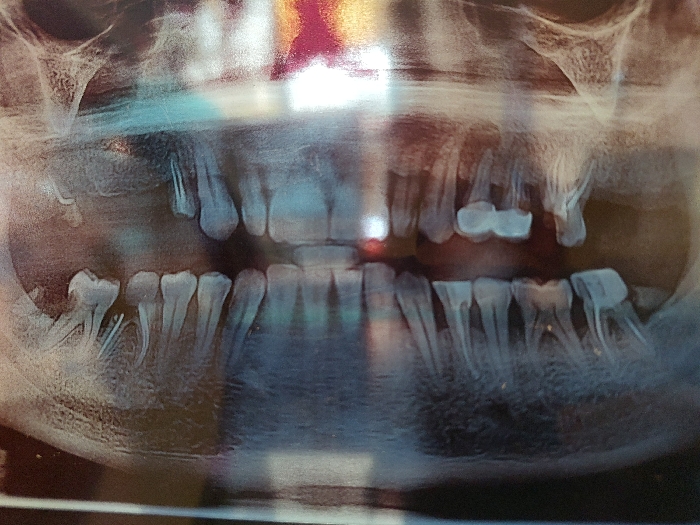

- "A panoramic dental radiograph (orthopantomogram) displays the human dentition, maxillary, and mandibular bone structures" by FM-24lPl1, licensed under CC BY 4.0

A panoramic dental radiograph (orthopantomogram) displays the human dentition, maxillary, and mandibular bone structures

A panoramic dental radiograph (orthopantomogram) displays the human dentition, maxillary, and mandibular bone structures. The image reveals numerous missing teeth, particularly in the posterior regions of both the upper and lower arches. Existing dentition shows evidence of multiple radiopaque dental restorations consistent with fillings and possibly crowns or prosthetic work. Visible tooth roots are present for the remaining teeth. The surrounding bone anatomy of the maxilla and mandible is discernible, including portions of the maxillary sinuses and temporomandibular joint areas. The image itself exhibits glare and reflections, suggesting it is a photograph of a physical X-ray film or digital screen. The location is Unknown, Unknown.